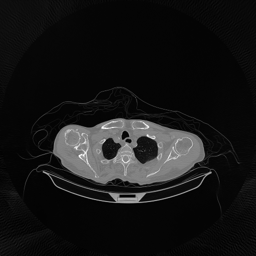

The results for simulated noisy data are shown in Fig. 2. The first and third rows display two representative slices from the test set, and the second and fourth rows present the corresponding error maps. The traditional WCE method suppresses cupping artifacts and recovers some missing anatomical structures but still shows noticeable deviations from the ground truth. Predictions from the four diffusion-based models demonstrate a markedly improved ability to restore anatomical structures. Among them, cDDPM fails to fully reconstruct the patient bed and retains residual noise in its outputs. This noise is attributable to an incomplete reverse denoising process rather than residual Poisson noise, as evidenced in our noise-free experiments (Fig. 5 in the Appendix). PatchDiffusion, diffusionGAN, and I2SB achieve similar visual quality, with I2SB producing the cleanest and most consistent reconstructions.

Quantitative results in Tab. V further confirm I2SB’s superiority over conventional deep learning methods such as FBPConvNet and Pix2pixGAN across RMSE, PSNR, and SSIM. Compared to other diffusion models—including cDDPM, PatchDiffusion, and cLDM—I2SB delivers higher image quality, while diffusionGAN achieves comparable quantitative performance. However, I2SB demonstrates a significant advantage in inference efficiency, as summarized in Tab. IV.

The experimental results on clinical head data are shown in Fig. 4. The reference images were reconstructed using the fast iterative shrinkage-thresholding algorithm (FISTA) with total variation regularization from non-truncated projection data. In the WCE reconstructions (Fig. 4(b)), severe truncation prevents accurate recovery of anatomical structures outside the FOV. Despite being trained solely on simulated data with a domain gap, all deep learning models can restore a substantial portion of the missing anatomy. Among them, the diffusion-based methods recover soft-tissue boundaries more faithfully than the conventional deep learning approach FBPConvNet, highlighting their stronger image generation capability. However, cDDPM reconstructions exhibit more noticeable noise than those from other methods, consistent with the simulated data results. The patchDiffusion model introduces artifacts within the FOV, likely due to its patch-wise processing strategy. While I2SB shares the same limitations as other diffusion models in perfectly restoring soft-tissue detail, it produces fewer residual noise patterns and fewer artifacts within the FOV boundaries. Overall, Fig. 4 demonstrates the strong efficacy of I2SB in reconstructing real CBCT data.